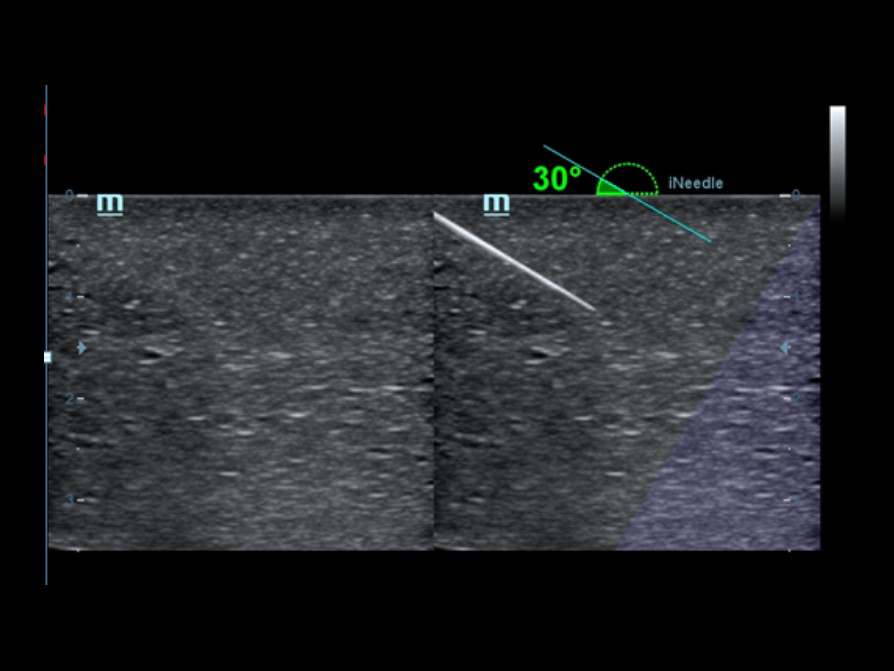

iNeedle?

?? ???? ??? ?? ??: ??? ?? ??? ???? ?? ? ?? ??? ?? ??? ??? ? ??? ???.

?????

iNeedle?(?? ?? ???)

?? ? ? ???? ???? B ??, ?? ??, PW ??? ?? ?? ?? ?? ???? ??? ? ????.